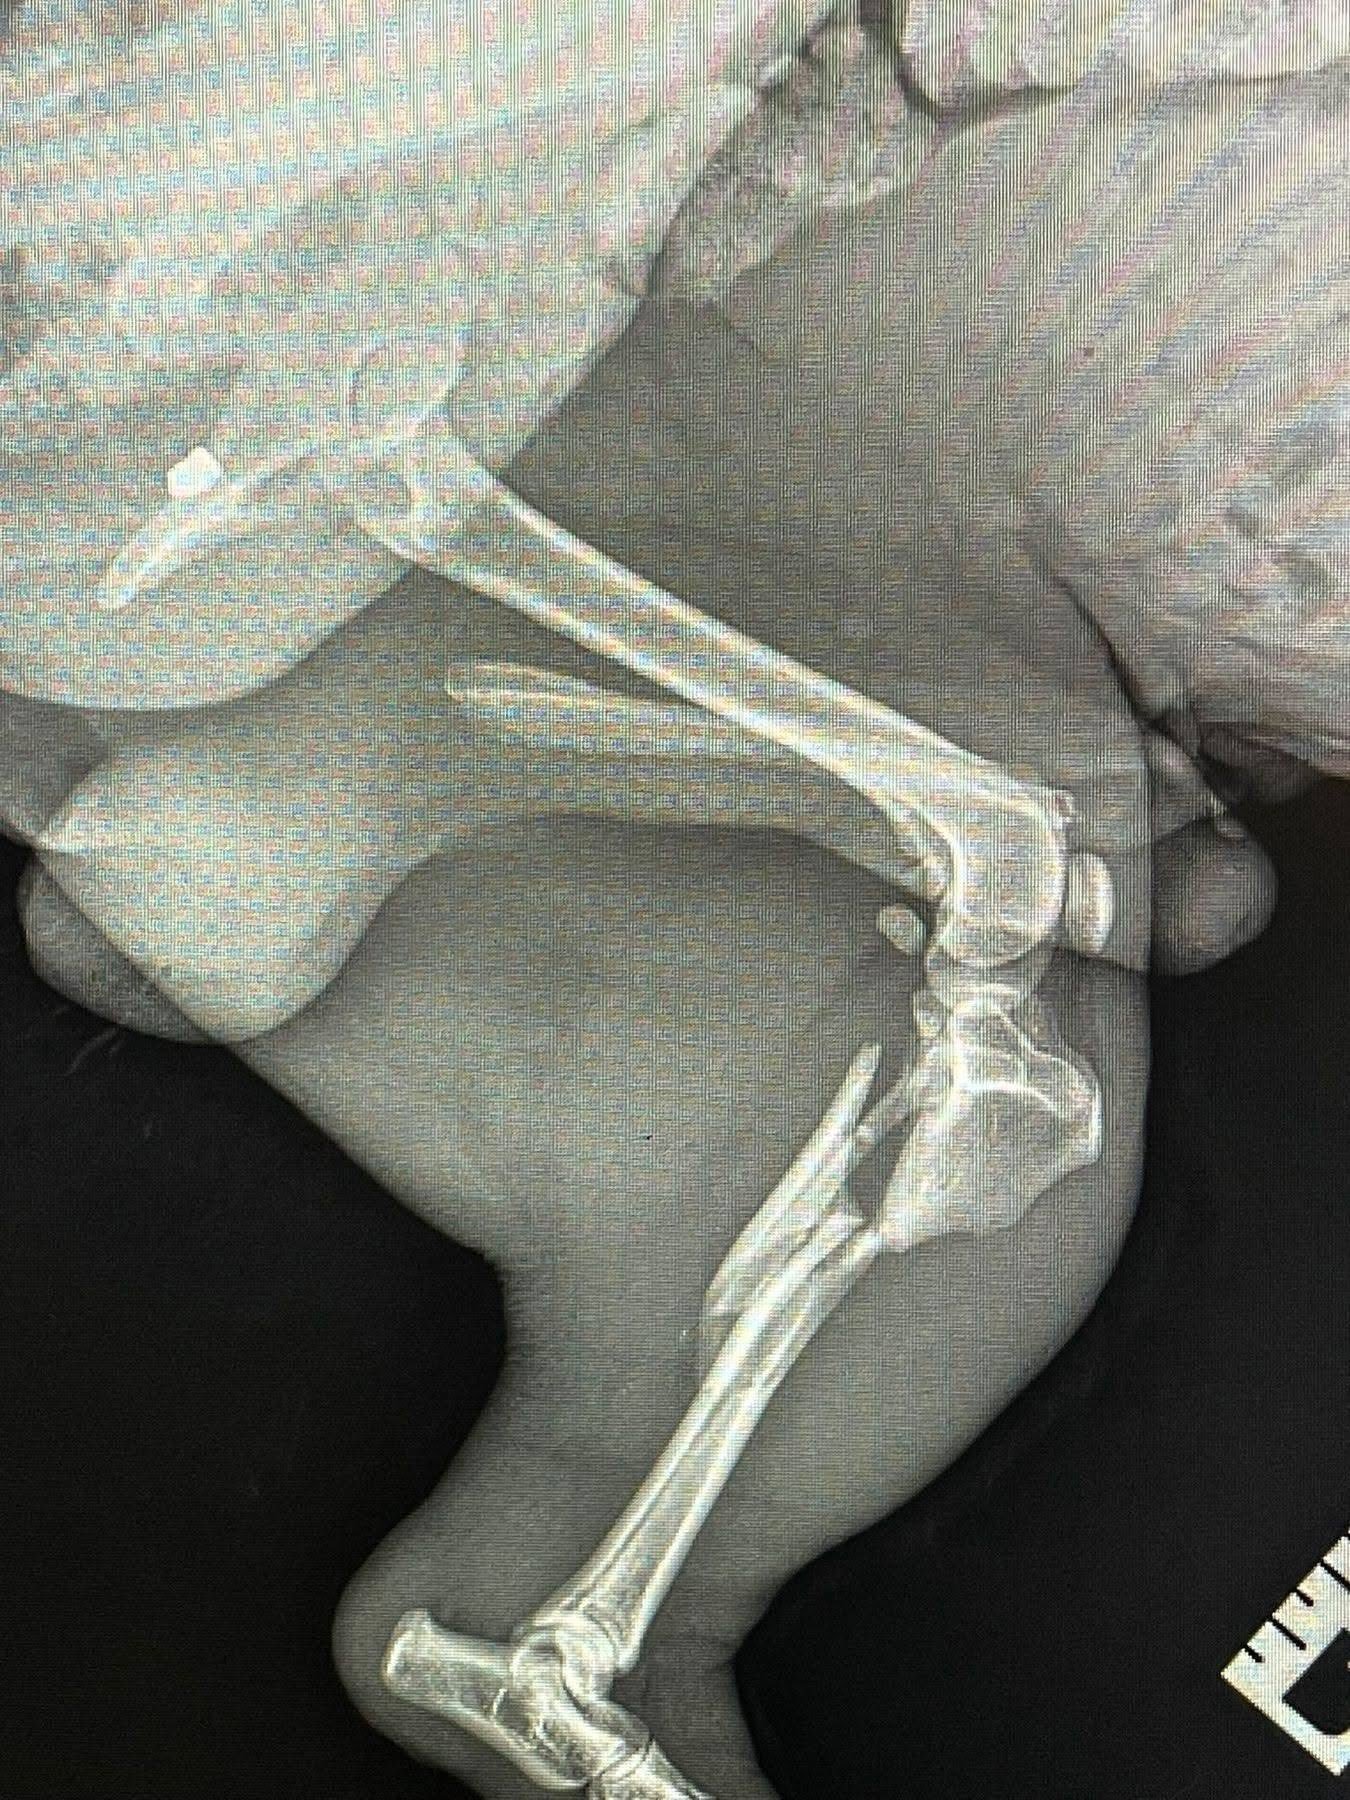

Як зазначено в дописі, огляд та рентген показали наявність у тілі тварини двох куль. Окрім цього, у собаки роздроблені кістки на лапі.